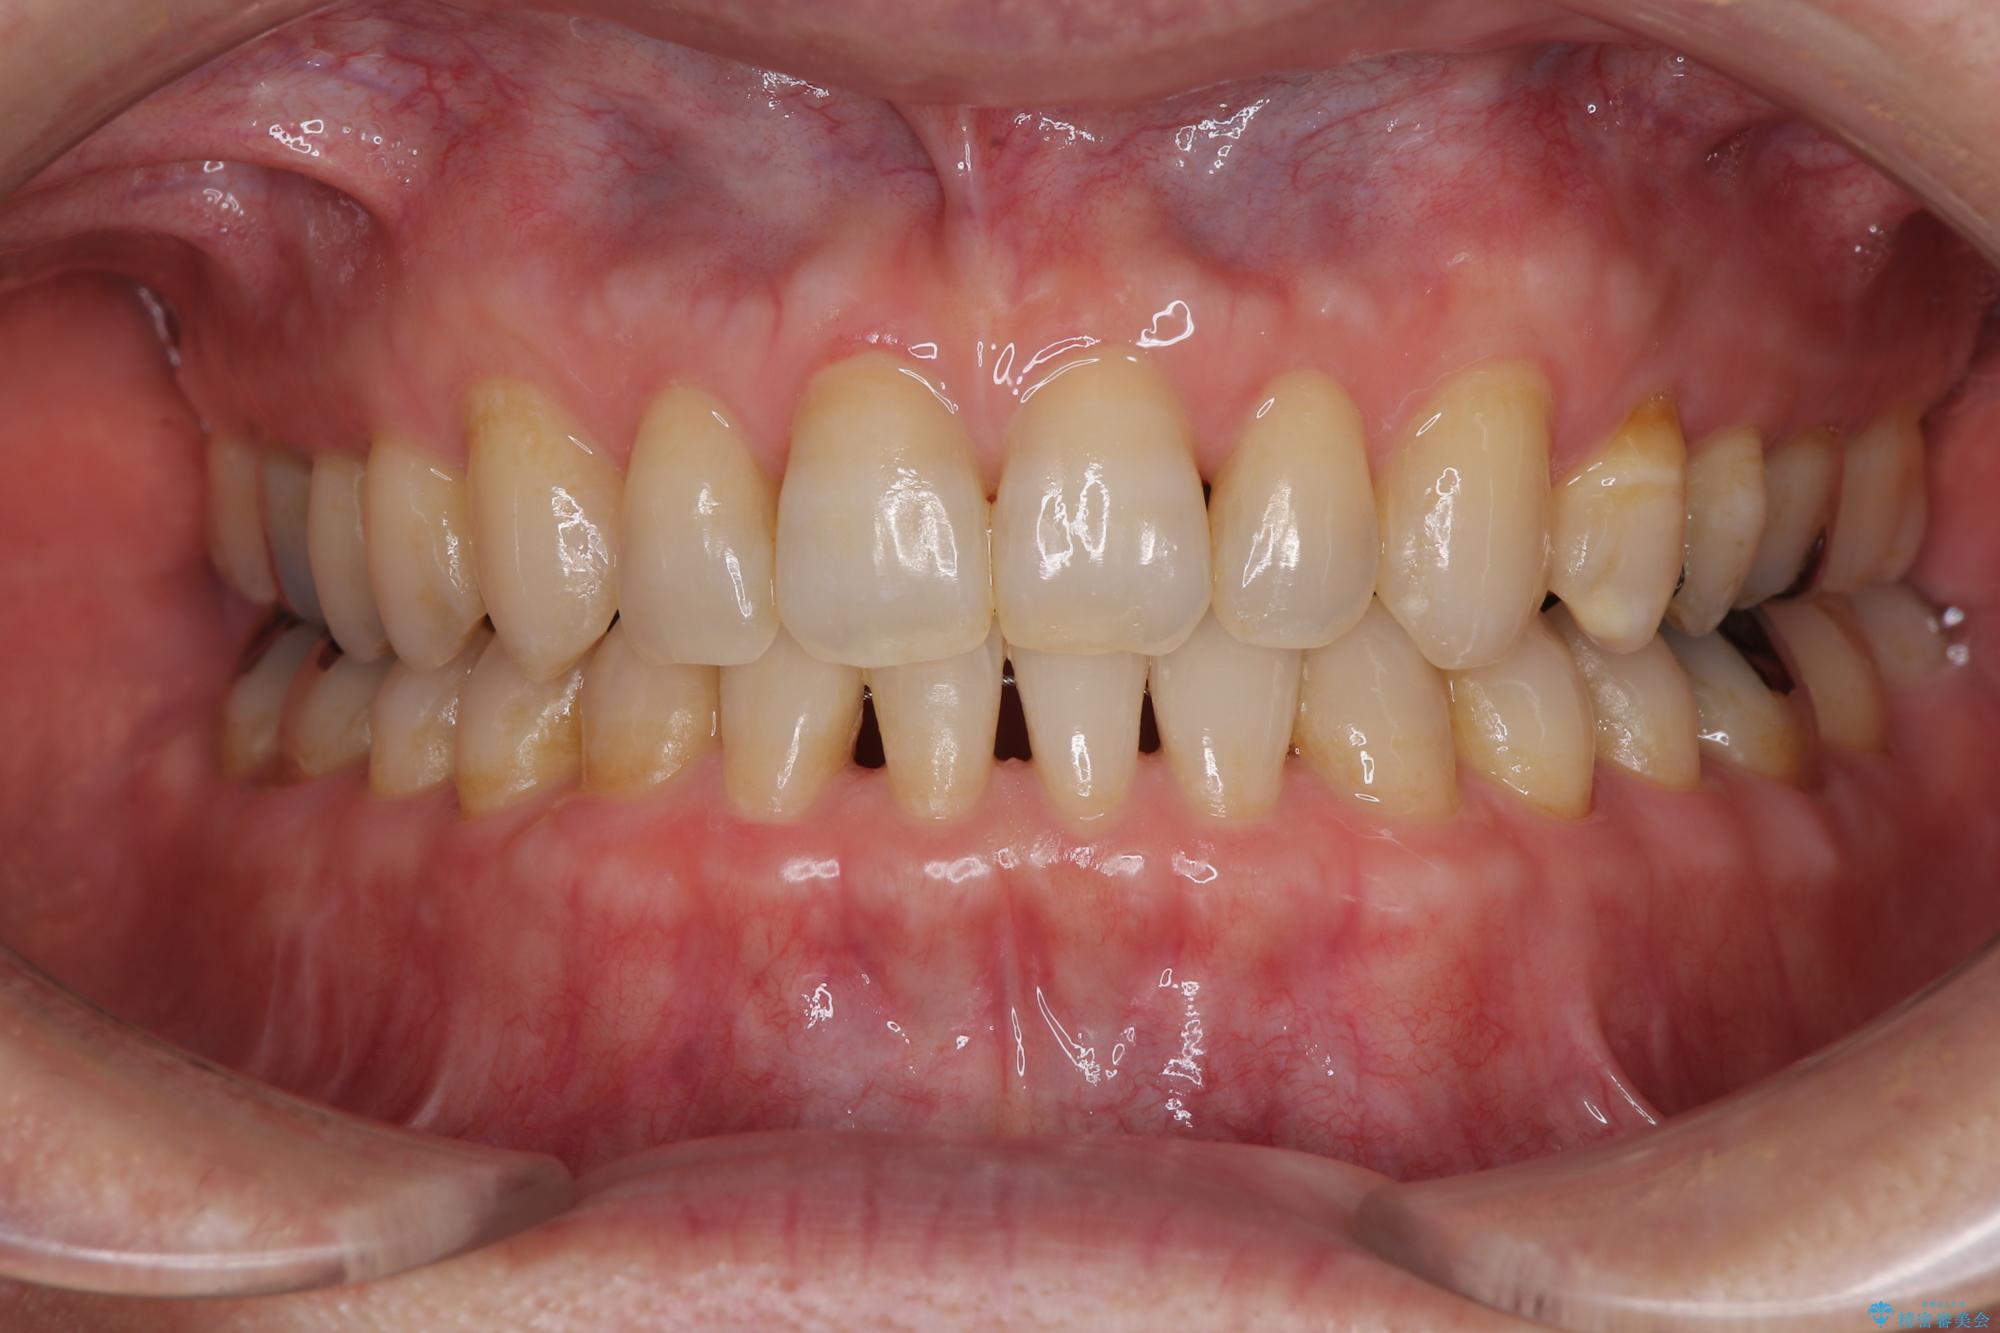

ディープバイトが改善され、睡眠時の食いしばりも緩和され、顎への負担が軽減されました。